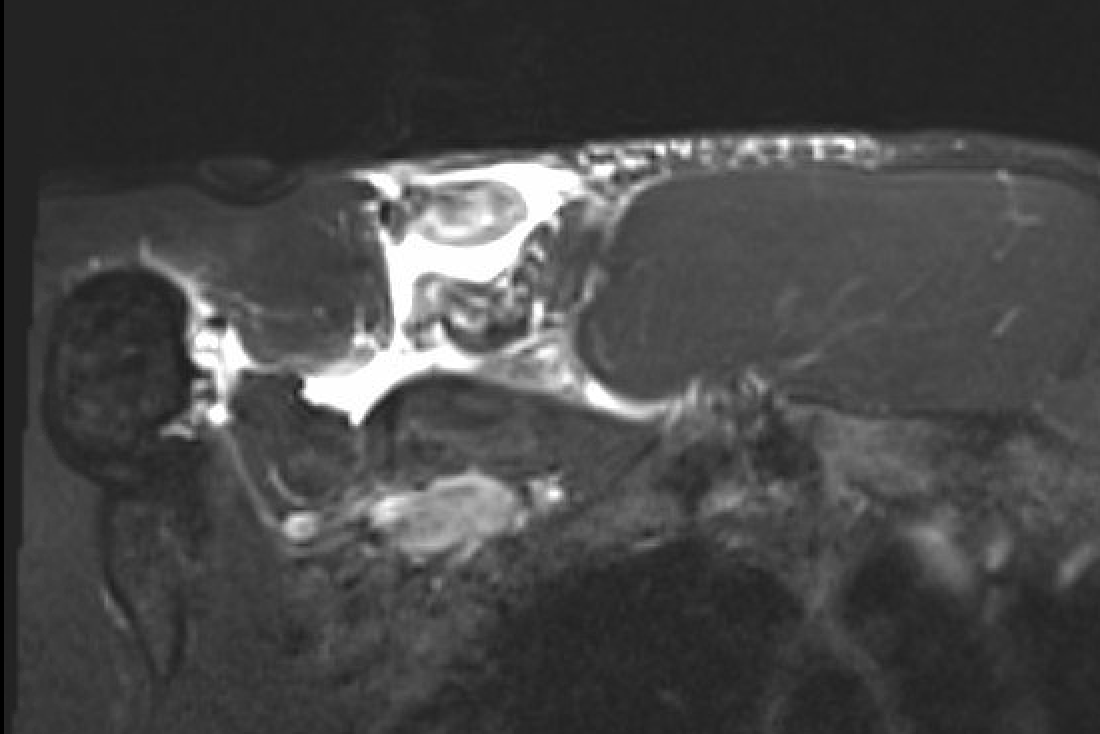

MRI

Coronal T2 Right shoulder demonstrating tendon avulsion of both sternal and clavicular heads

Axial T2 Right shoulder demonstrating tendon avulsion of both sternal and clavicular heads

Coronal T2 MRI Right shoulder demonstrating musculotendinous avulsion